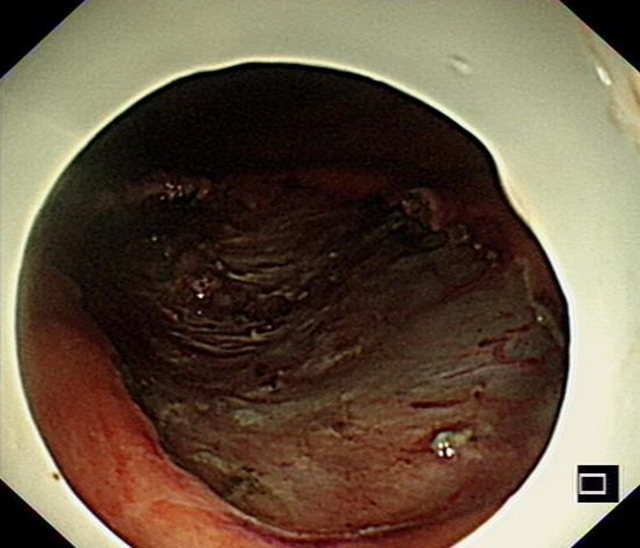

1月后复查CT与胃镜,患者瘤体有明显缩小,并且供血的主要动脉血管已经完全被栓塞。

CT检查提示体内的胃黏膜下肿瘤有所缩小,意味着栓塞成功。而后,汤小伟副教授为李婆婆进行内镜下ESD切除术。他带领团队在患者胃黏膜表面开一个小口,内镜经由这个小口在黏膜下层建“隧道”直至肿瘤位置,再将肿瘤和周边组织分离后切除取出。50分钟左右,手术顺利完成。最终的病理结果提示肿物的性质为胃间质瘤(低危险度),属于预后较好的一种类型。